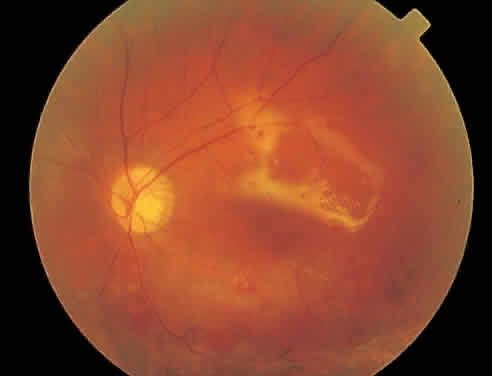

Fig. 1. Typical appearance of peripapillary cytomegalovirus retinitis with hemorrhage and exudate. Despite the proximity to the optic nerve, the visual acuity was 20/20 (6/6) and the patient had no symptoms.

Over a course that usually spans weeks, infiltrates of CMV tend to assume two different patterns of clinical disease.11,12 The first pattern is called hemorrhagic and is characterized by broad geographic zones of retinal whitening. These large, geographic lesions are usually in close proximity to a major retinal blood vessel or the optic nerve. Satellite lesions are common. When the retinal necrosis associated with CMV retinitis becomes widespread, it is almost invariably associated with retinal hemorrhages. Although the border between necrotic and unaffected retina is sharply demarcated, the border itself appears irregular and jagged. Exudation into the retina or subretinal space may be seen, adding to the granular appearance of the retinitis. Juxtaposition of large zones of white, granular necrosis with those of red retinal hemorrhage has led this appearance of CMV retinitis to be described as either “pizza-pie” or “cheese and ketchup.” The retinal blood vessels, both arteries and veins, in the areas of necrosis commonly appear sheathed, secondary to a vasculitis. As a consequence, secondary retinal vascular occlusions, especially branch retinal vein obstructions, may occur in the course of CMV retinitis. Immune-mediated vascular damage may play a role in the vasculitis.12 Central healing of these lesions will occur as the infection progresses. Avasculitis resembling “frosted branch angiitis” hasbeen reported (Fig. 2).28 A second pattern of CMVretinitis has been labeled “granular” or “brushfireborder.” In this appearance, the focal granular infiltrates enlarge slowly across a line, leaving ever-increasing areas of destroyed retina and atrophic retinal pigment epithelium behind. Hemorrhages and vitreous cells are a less prominent feature. There appears to be direct cell-to-cell transfer of infected virions in this pattern of infection (Figs. 3 and 4). The brushfire border is commonly seen in CMV retinitis lesions anterior to the equator (Fig. 5). The significance, if any, of these two clinical patterns of CMV retinitis is not known, and, in some eyes, both patterns of disease can be seen simultaneously or in sequence. Progression of retinitis has been defined in clinical trials as movement of a lesion border at least 750 μm along a front that is 750 μm or more in length, development of a new CMV lesion in a previously involved eye or in the uninvolved fellow eye of a patient with baseline unilateral disease.29 Without treatment or improvement in the host's immune system, CMV retinitis is a relentless, slowly progressive infection resulting in blindness caused by total retinal necrosis, retinal detachment, or optic nerve involvement, in any combination.

Fig. 2. Active cytomegalovirus retinitis concentrated around the optic nerve. Temporal to the fovea, there is perivascular whitening with a frosted branch angiitis appearance.